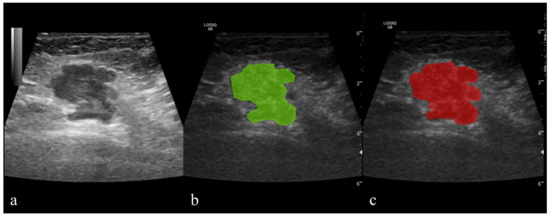

2.5.1. Image Pre-Processing and Segmentation